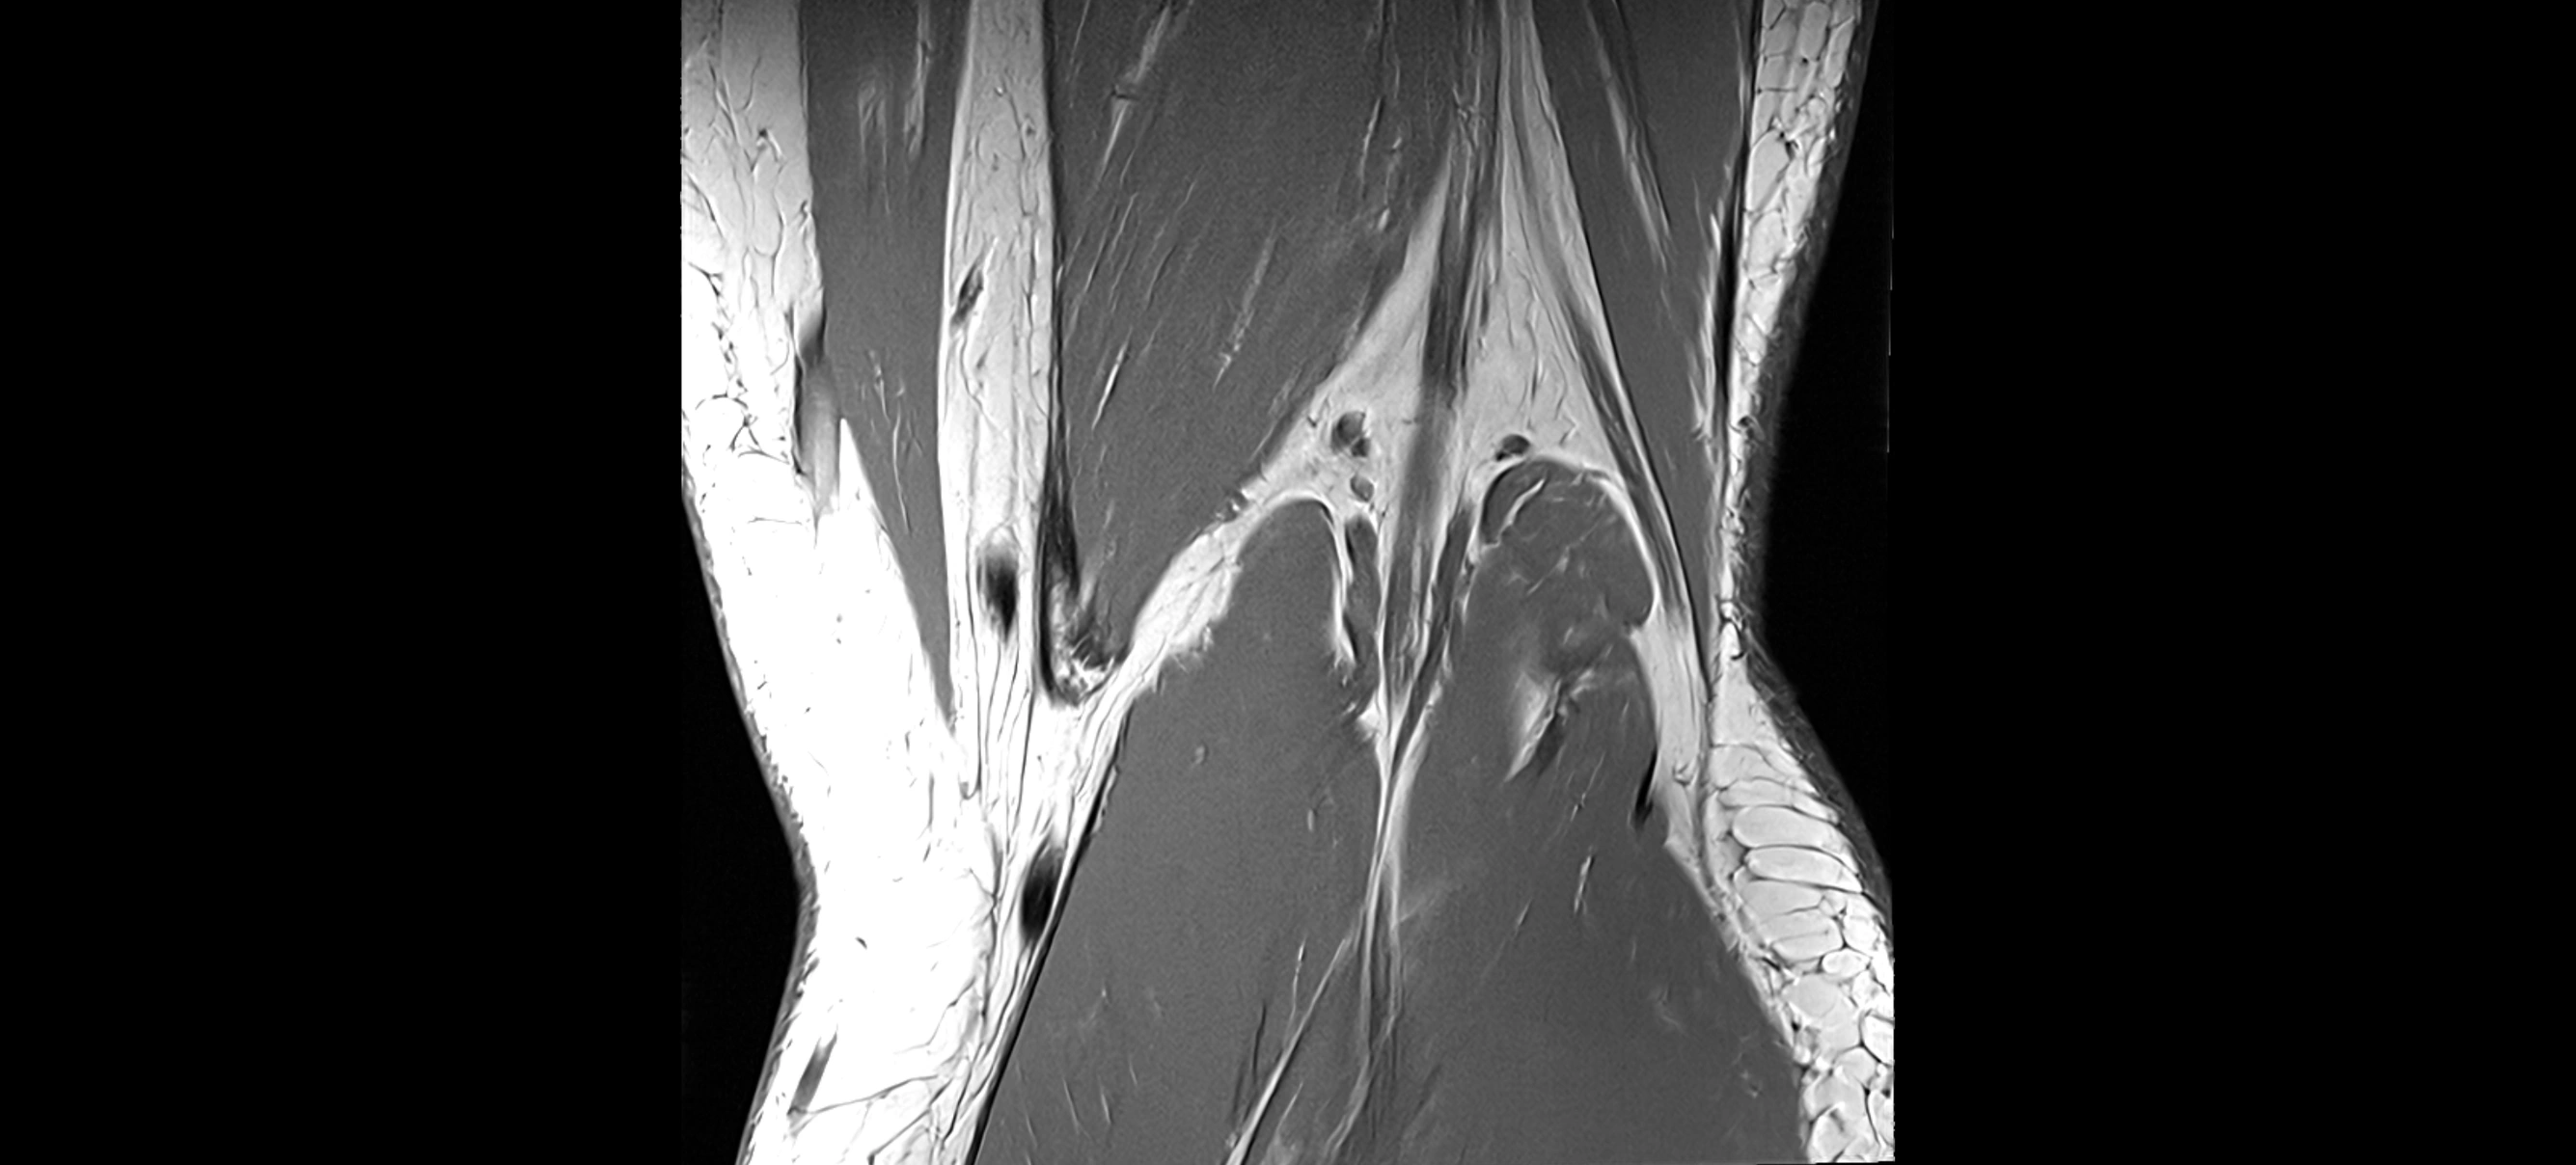

MRI images

image